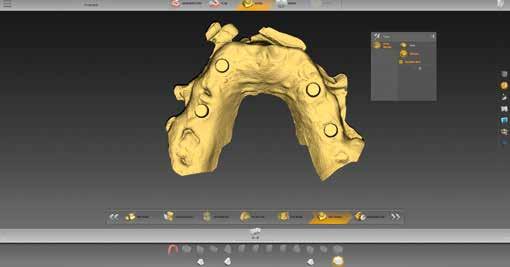

1–2. ábrák: A BioCopy és a felső állcsont beolvasása.

szükséges információ rögzítésére megfelelt. A meglévő pótlásról is készült egy ún. BioCopy-Scan (1. ábra), amelyet összevetíthetünk a felső állcsontról készült, az adhezív sapkákat is tartalmazó beolvasással (Atlantis Conus Abutment, Dentsply Sirona). Így meghatározhattuk a vesztibuláris szituációt és a vertikális helyzetet, ami megkönnyíti a funkcionális és esztétikai szempontból is kiemelkedő munka elkészítését. Ellenőriztük a meglévő pótlás egyensúlyát és érintkezési pontjait (3–4. ábrák), meghatároztuk a minta tengelyét (5. ábra), majd az adatokat az inLab szoftverbe importáltuk.